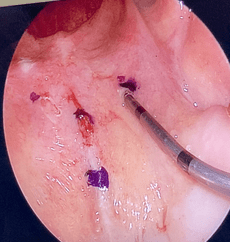

COBLATION Assisted Surgeries

A minimally invasive, low thermal technology for effective dissection and removal of tissue, COBLATION Technology has been used for ENT procedures such as tonsillectomy, turbinate reduction, laryngeal lesion debulking and soft palate.

While conventional electrosurgical devices use high temperatures to remove and cut tissue, our COBLATION Technology creates a controlled, stable plasma field to precisely remove tissue at a low relative temperature, resulting in minimal thermal damage to surrounding soft tissues. Its features include very limited depth of thermal penetration; minimal collateral tissue damage; localised effect; and controlled, volumetric tissue removal. Coblation is often preferred for its ability to reduce surgery duration and pain, minimise bleeding, and speed up recovery times in patients undergoing certain types of surgery.